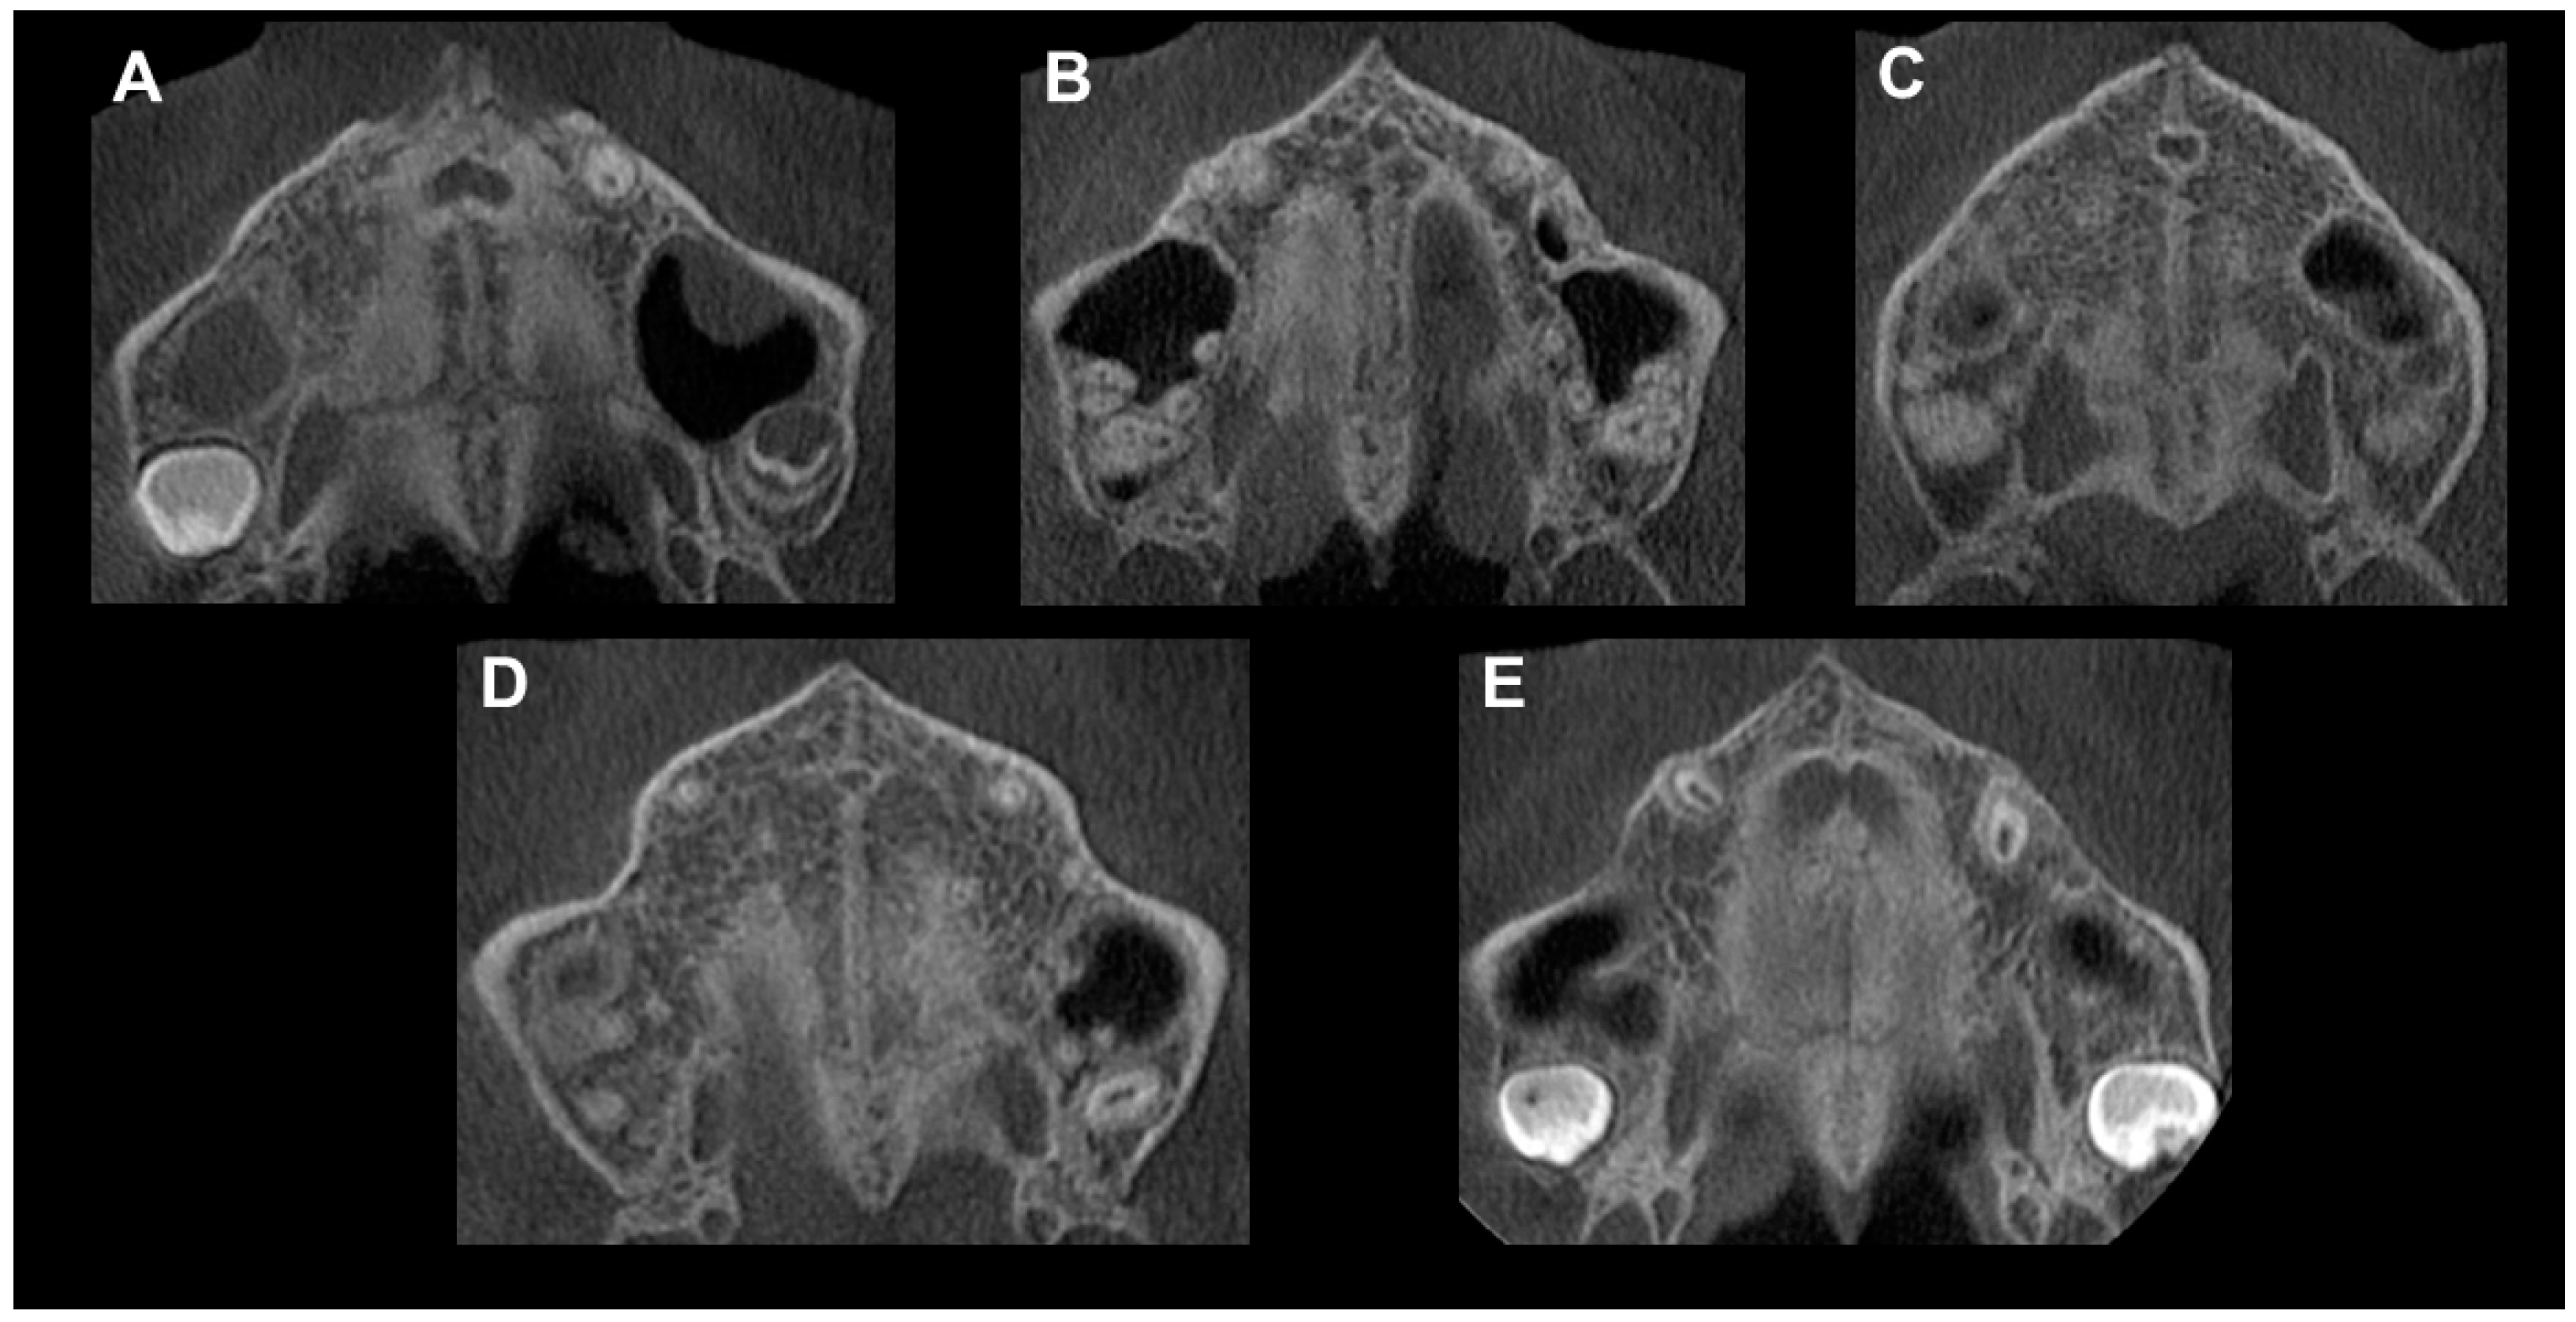

Figure 1. Anterior axial cut—palatal processes of the maxillary bone.

Figure 3. Method of Angelieri et al. [40] in CBCT. (A) The midpalatal suture is seen as a relatively straight radiopaque line. (B) The midpalatal suture appears as a scalloped line of high density. (C) Two radiopaque, scalloped and parallel lines are separated by areas of low radiographic density. (D) The palatine bones become more radiopaque, and the suture is not visualized in this sector; it is only visualized as two scalloped high-density lines at the midline on the palate bone. (E) It is no longer possible to see the suture along the maxillary and palatine bones, which indicates that fusion has occurred in the maxilla.